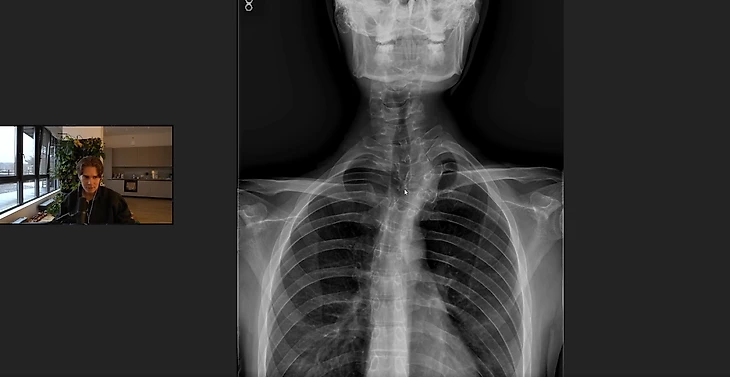

• Nix показал рентген своего сколиоза: «Я ходил к лучшим врачам России, каждый мне сказал: «Чувак, тебя не спасти»

Nix показал рентгеновский снимок своего искривления позвоночника.

Александр «Nix» Левин поделился, насколько у него сильные проблемы со спиной.

«Все, что вы советуете, не работает на меня. У меня врожденное серьезное искривление позвоночника. У кого-то грыжа, но это гигантская разница между тем, что есть у меня. Все, что вы советуете, не будет работать.

Я ходил к лучшим врачам России, каждый мне сказал: «Чувак, тебя не спасти», – поделился Nix.

Ранее Nix поделился, что ему насчитали 17 млн рублей за лечение спины в клинике доктора Блюма в Испании